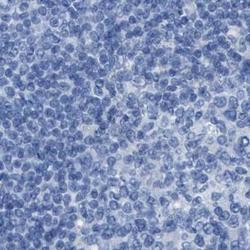

- Immunohistochemical staining of ASGR1 in human gastrointestinal using ASGR1 Polyclonal Antibody (Product # PA5-52994) shows no positivity in glandular cells as expected.

- Immunohistochemical staining of ASGR1 in human lymph node using ASGR1 Polyclonal Antibody (Product # PA5-52994).